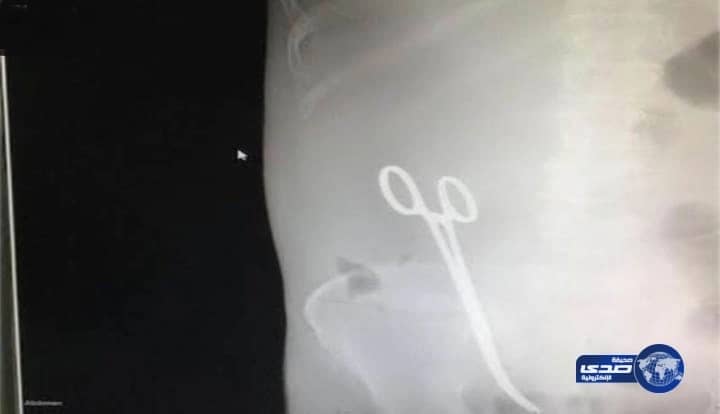

كشف المتحدث الإعلامي لإمارة منطقة حائل متعب المرشدي، أن أمير المنطقة الأمير سعود بن عبدالمحسن بن عبدالعزيز يتابع مجريات التحقيق في حادثة نسيان مقص في بطن مواطن بمستشفى الملك خالد بحائل.

وأوضح المرشدي في تصريحات نشرت اليوم الأحد عبر حساب إمارة حائل على "تويتر"، أن أمير المنطقة وجه بمتابعة التحقيقات حول واقعة نسيان مقص داخل بطن المواطن محمد الحائطي عقب إجراء عملية جراحية له بمستشفى الملك خالد بحائل، مؤكداً أن التحقيقات حول الواقعة ما زالت جارية.

وكانت الشؤون الصحية بحائل أعربت في بيان لها الخميس الماضي عن اعتذارها للمواطن عن نسيان طبيب لمقص داخل أمعائه، مؤكدة أنها سجلت هذا الخطأ الطبي على برنامج الأحداث الجسيمة بوزارة الصحة، وأنها شرعت في التحقيق حول الحادثة، تمهيداً لمحاسبة المتسبب، كما منعت كل من له صلة بالواقعة من السفر للخارج.